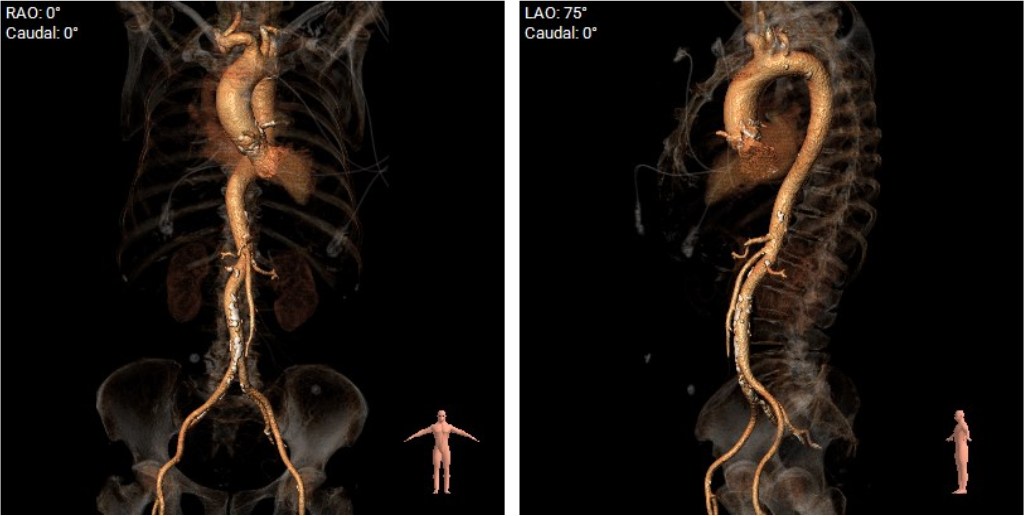

主动脉弓:

股动脉入路:

该患者瓣环最小径22.4mm,且瓣叶重度钙化,此外左无冠窦之间有一处柱状钙化延伸至LVOT,决定术中用20mm球囊预扩,评估冠脉风险和指导瓣膜选型。此外,患者双侧瓣叶长度均大于冠脉高度,且左冠团状钙化,冠脉遮挡高危,拟在TAVR前行左冠支架保护。

主入路:右侧股动脉

辅入路:左侧股动脉